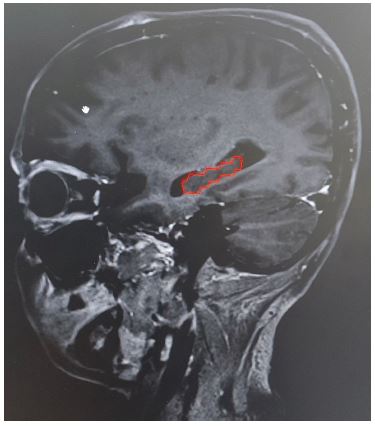

Radiologically, the hippocampus appears hypointense on T1 weighted MRI images (Figure 1). It appears as a curved banana shaped structure in axial MRI sequences. The hippocampus remains medial to the temporal horn of the lateral ventricle throughout its extent. The anterior boundary of the hippocampus is defined by the anterior edge of the temporal horn. The medial boundary of the hippocampus is defined by the “boomerang-shaped” uncus and posterocranially quadrageminal cistern.

Figure 1: Hippocampus appearing hypointense on T1 weighted MRI image.